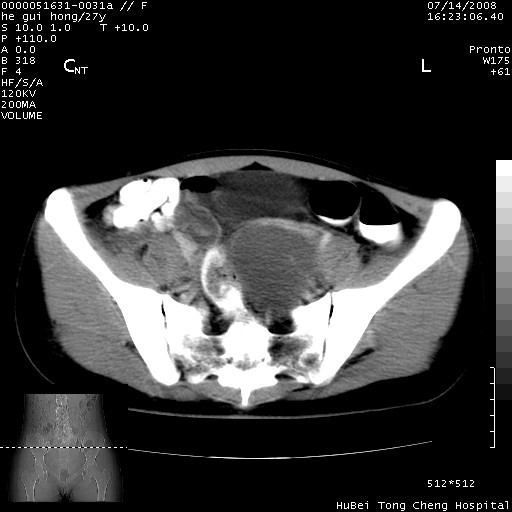

以下是引用杀毒软件在2008-7-20 8:03:00的发言:[br]支持双侧卵巢囊腺瘤可能性大!

以下是引用zjzjr在2008-7-20 13:36:00的发言:[br]双侧附件囊腺瘤可能性大!